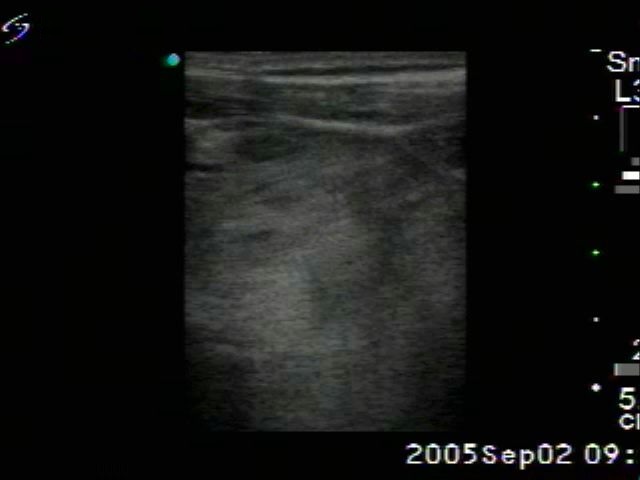

Benign nodular hyperplasia - Case 33. |

Clinical presentation: a 76-year-old man with hoarseness. The goiter was known for decades and grown slowly. Laryngology revealed palsy of the left nervus recurrens.

Palpation: both lobes of the thyroid were highly enlarged and nodular.

Ultrasonography: a multinodular goiter with both retrotracheal and substernal spread.